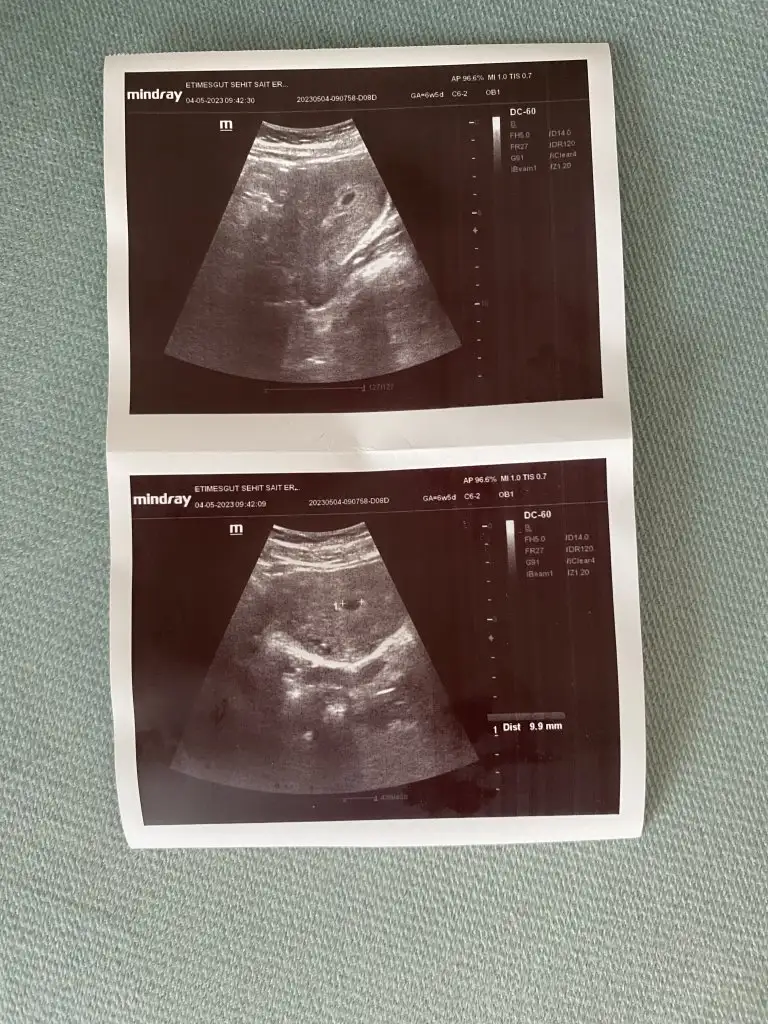

Benim de sat 22 Mart. Cuma günü gitmiştim doktora. Sata göre 6+2 ydim. Siz de 6+3 olmanız gerekiyor doktora gittiğiniz gün. Benim kesem 8.6 mm idi ve doktora kese için çok iyi dedi. Biz de yolk ve bebek göremedik ama doktor olumsuz konuşmadı ve haftaya gel dedi. Sizin neden kese için haftayla uyumlu değil demiş doktor acaba? Ultrason resmi var mı acaba?

Sizin sat 18 Mart. Kese 9 mm. Haftayla uyumlu değil demiş.

Çok iyi yapmışsın farklı bir doktora gitmeyi düşünerek. Ultrason resmi var mı acaba

Eklentiler

• 64A58F25-866E-4677-875B-E42968B7D0B2.webp

64A58F25-866E-4677-875B-E42968B7D0B2.webp

86,7 KB · Görüntüleme: 357